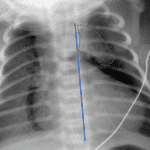

Age: 3 months

Sex: Male

Indication: Fever

- Mild hyperinflation and peribronchial thickening without focal airspace opacification or pleural effusions

- Normal thymus overlying the right lung apex

- Normal thymus

Mild hyperinflation and peribronchial thickening without focal airspace opacification or pleural effusions, which can be seen with a viral infection.

Normal thymus overlying the right lung apex.